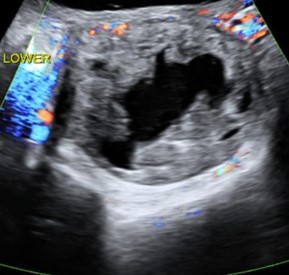

Figure 4: Ultrasound with Doppler showing complex cystic architecture previously attributed to ovarian pathology.